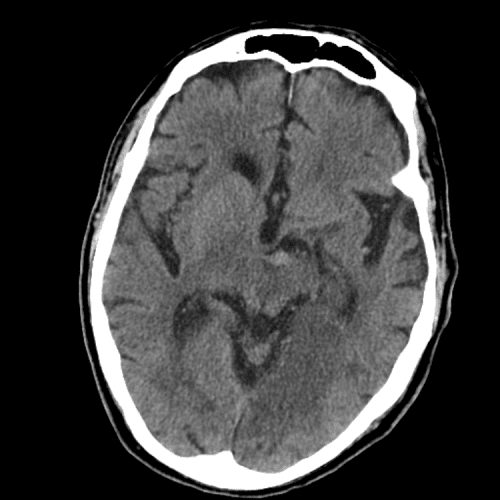

Watershed ischemia

Deep venous infarct

cerebral edema